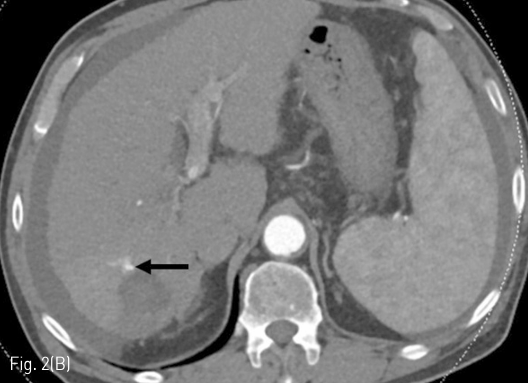

Fig 2B

Follow up liver CT 11 months after RFA. (A-D) There is a connection (arrows) between a branch of the S7 segmental hepatic artery and right posterior portal vein.

정기적 추적검사로 시행한 자기공명영상 (MRI)에서 7번 간분절(S7)에 간담도기에 저신호강도로 보이고 확산강조영상에서 고신호강도로 보이는 간암으로 의심되는 결절이 발견되어 고주파 열치료술이 시행되었다 (Fig. 1A, 1B). 10개월 후 추적검사로 시행한 전산화 단층 촬영의 동맥기 영상에서 우측 후방 간문맥이 주위 간동맥만큼 조영증강이 되는 소견을 보이고 있다(Fig. 1C, 1D). 동맥기 영상에서 간동맥과 간문맥 사이에 연결성이 보여 간동문맥단락이 의심되는 소견을 보이고 있다(Fig. 2).